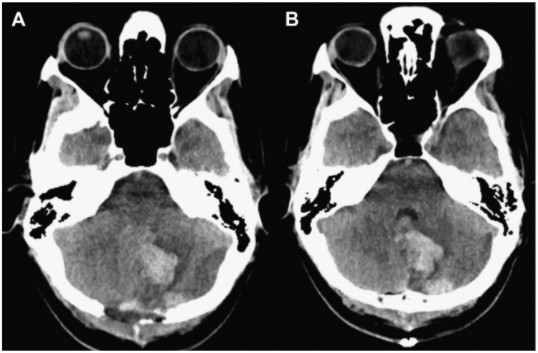

两天后,患者临床状况恶化,嗜睡、上视麻痹和双侧第六神经麻痹。NCCT 复查(图 2)显示后颅窝有脑积水和占位效应,并有脑干移位的证据。甘露醇的给药没有任何显著变化。紧急行 SDC 手术。术后(图 3),患者临床检查有所改善。减压后大约 2 天,临床症状仅表现为轻度的辨距障碍和步态。

图 2 左侧 PICA 梗死。(A)组织肿胀和占位效应导致后颅窝消失第四脑室受压。(B)梗阻性脑积水伴颞角扩张、脑沟消失和脑干前移。